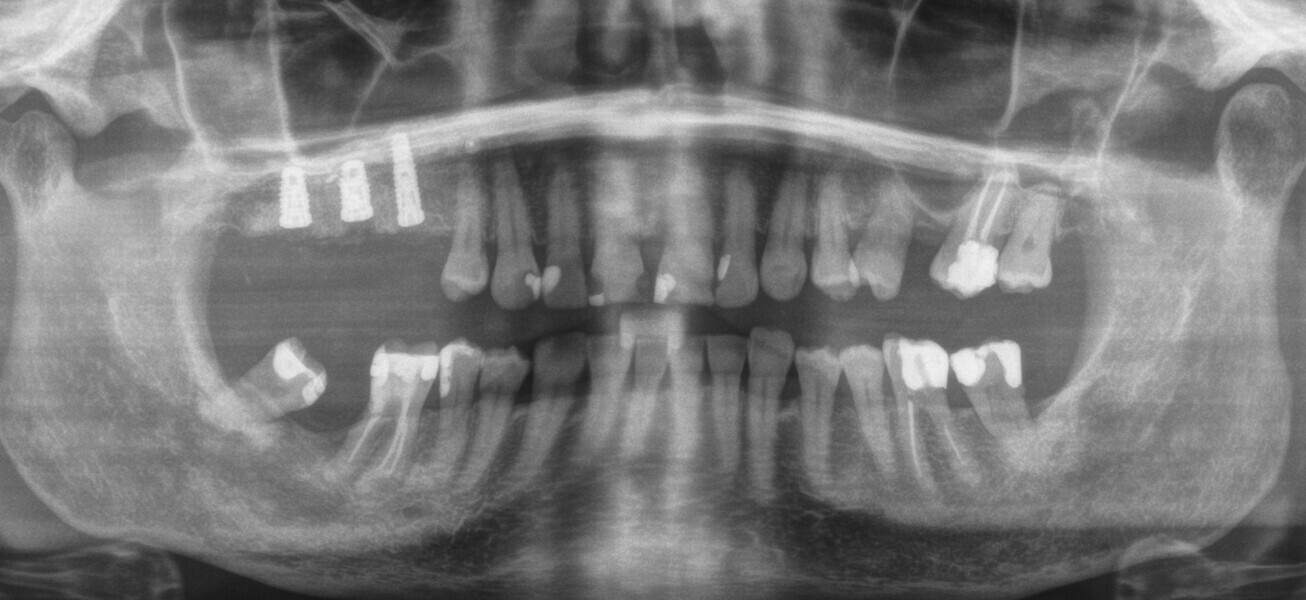

A 62-year-old female patient (ASA Class I), a non-smoker and with normal glucose levels, with previously treated periodontal disease presented for implant and prosthetic rehabilitation of the upper jaw (Fig. 1). Radiographic analysis, performed through a dental panoramic tomogram and CBCT scan, revealed the presence of a vertical bone defect in the right posterior sextant, due to the complete loss of the alveolar process (Figs. 2; 3a & b). The clinical examination showed the severity of the bone defect, which had resulted in an obvious volume deficiency in both the horizontal and vertical dimensions (Figs. 4 & 5).